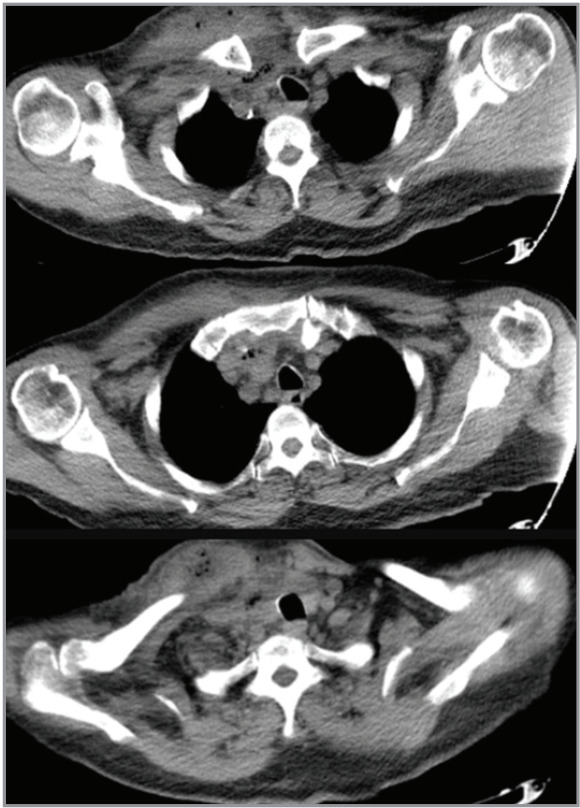

Endobronchial ultrasound-guided transbronchial needle aspiration (EBUSTBNA) is a minimally invasive diagnostic tool used for the evaluation of mediastinal lymphadenopathy. It is a safe procedure, but complications such as bleeding and infection may occur. We report a case of a patient who developed a subcutaneous abscess abscess and mediastinitis after EBUSTBNA. A 75-year-old male with a history of right nephrectomy due to renal cell carcinoma and lung adenocarcinoma history underwent EBUS-TBNA for the evaluation of a right upper paratracheal lymph node. Two weeks after the procedure, the patient presented to the emergency department with skin induration and erythema on the right clavicular area. A non-contrast neck and thorax CT scan was performed, which revealed an extensive subcutaneous abscess on the right clavicular area, extending to the supraclavicular region. The patient was hospitalized, and empirical intravenous antibiotics were initiated due to deep neck infection. Repeated drainage of the subcutaneous abscess was performed. Bacteriologic examination revealed Streptococcus mitis. The patient showed improvement with antibiotic treatment, and a follow-up ultrasound showed a decrease in the size of the abscess and was discharged approximately four weeks after hospitalization. Although very rare, serious infectious complications may develop after EBUSTBNA, and our case report is an important example regarding its management process.